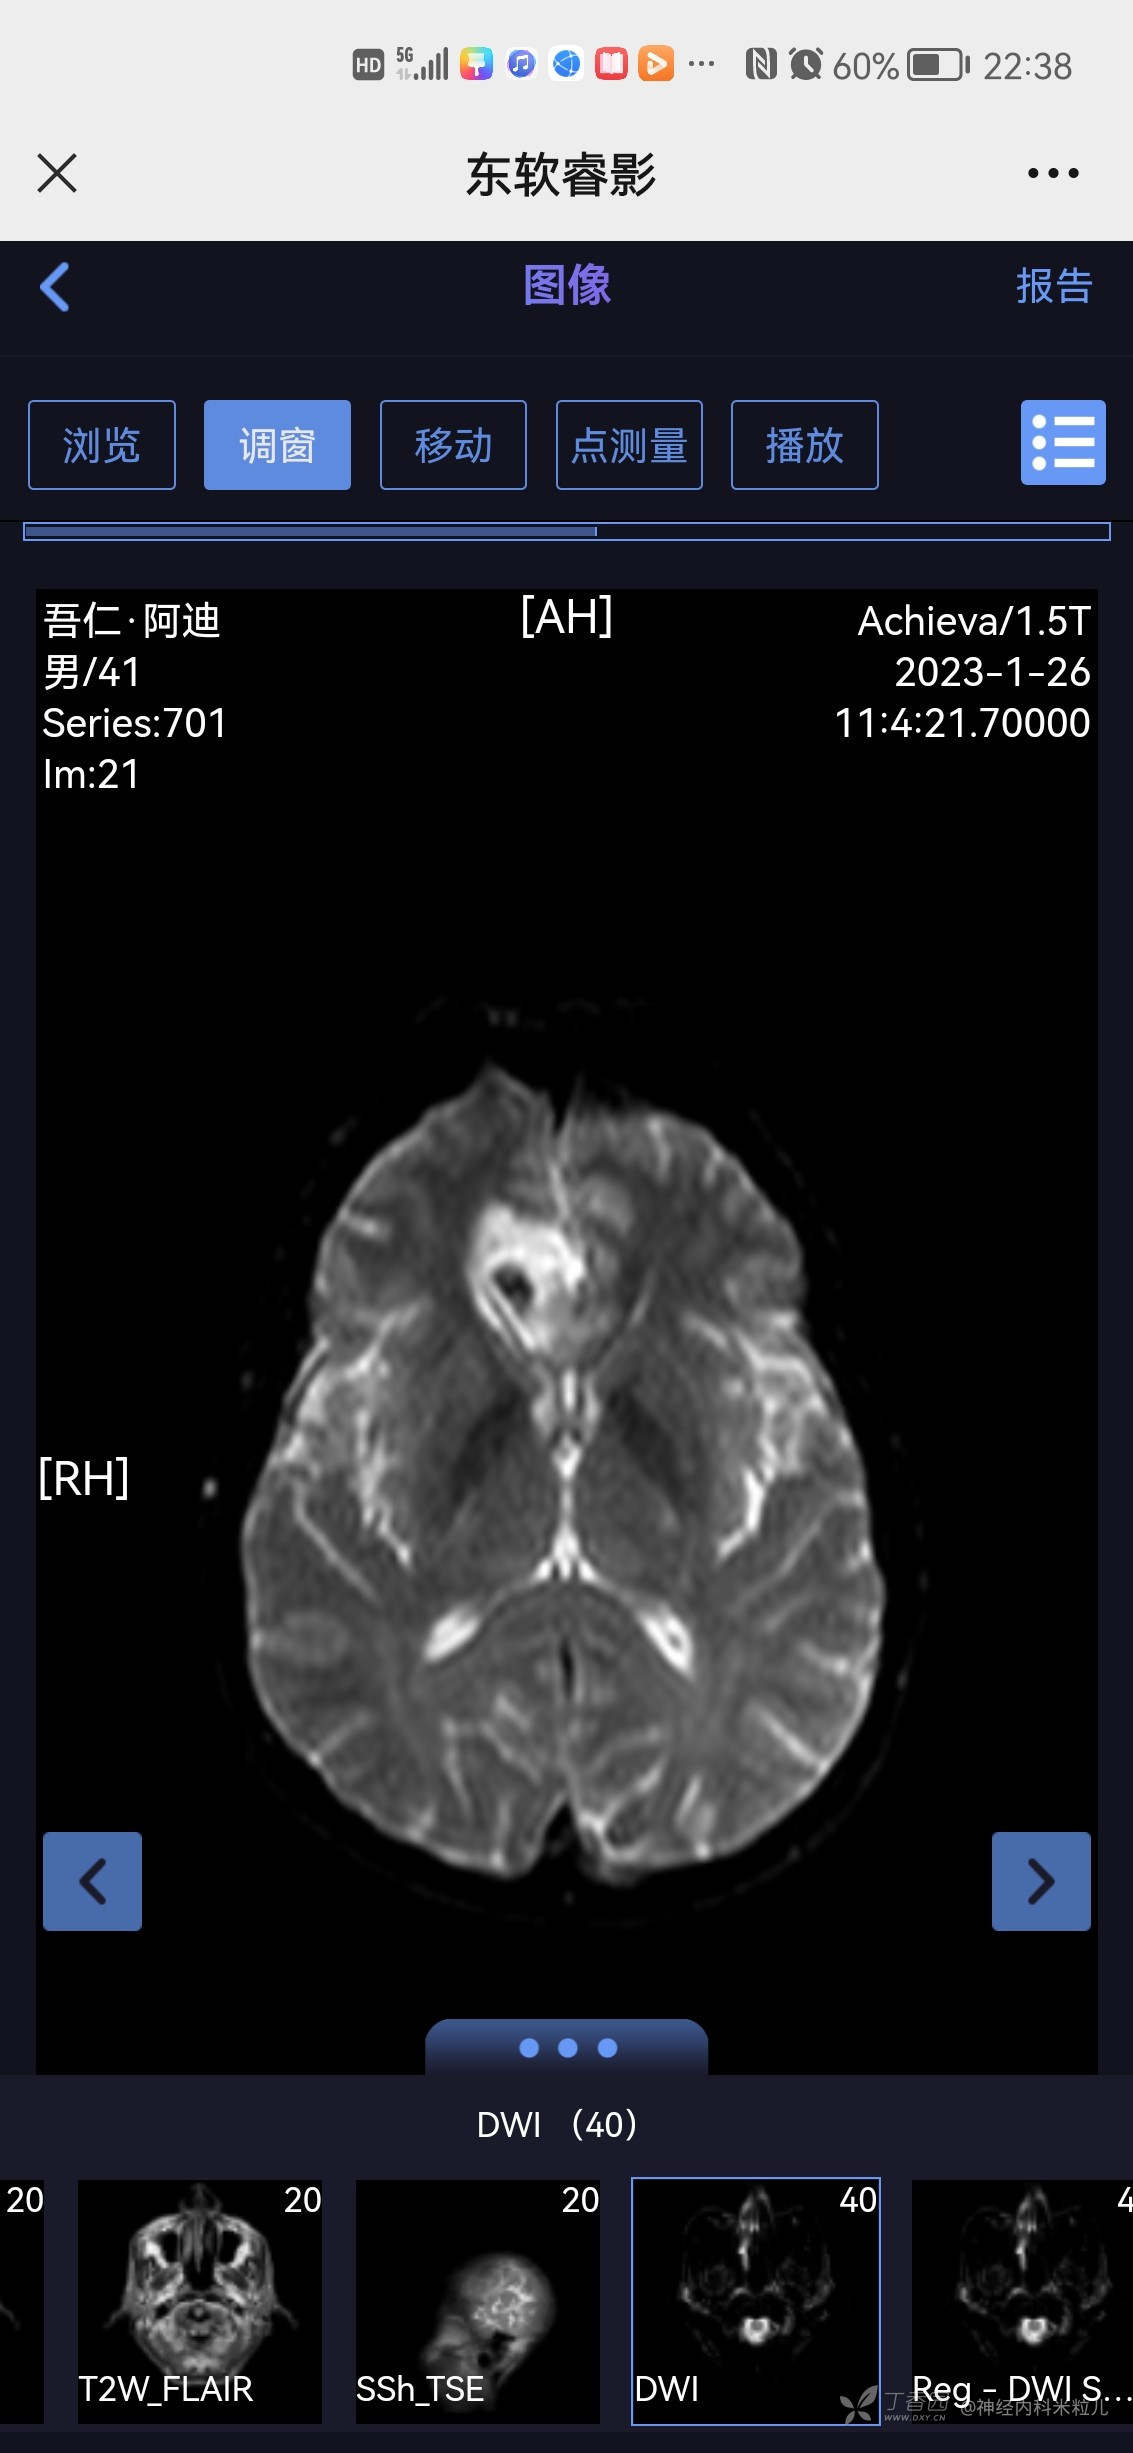

2023年1月18日我院头颅核磁提示:颅内多发异常信号,考虑:感染性病变,建议增强检查。}